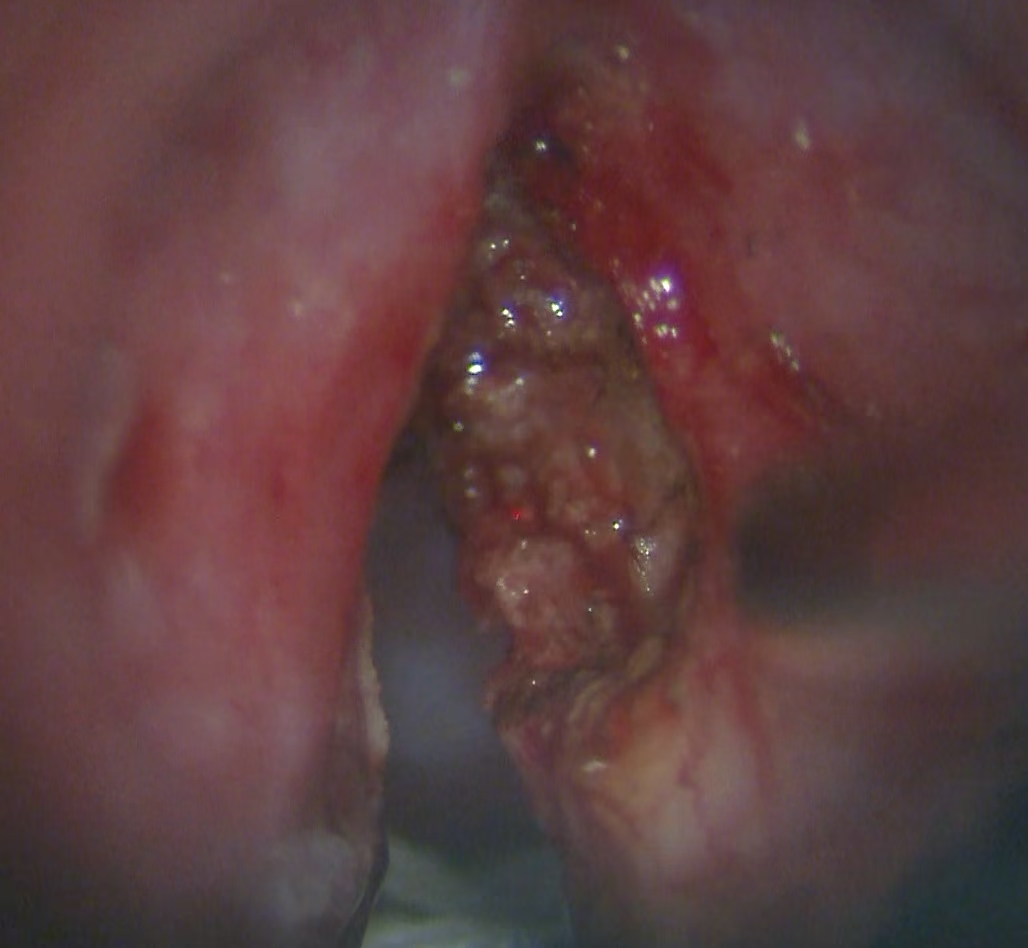

声带疾病(含咽喉早癌)的显微微创手术

由王刘倩医师团队牵头,该团队擅长使用显微镜辅助技术,对各类声带疾病进行精准的诊疗与手术。

其核心特色在于声带息肉切除术及激光切除血管性瘤或糜烂组织,这些方法能在最大限度保留声带本身结构和功能的情况下,彻底清除病变组织。

在显微缝合技术方面,该团队可精确到毫米级别,手术后患者能快速康复并持续改善发音质量。这种高超技艺使得王刘教授团队成为声带疾病治疗领域的佼佼者。